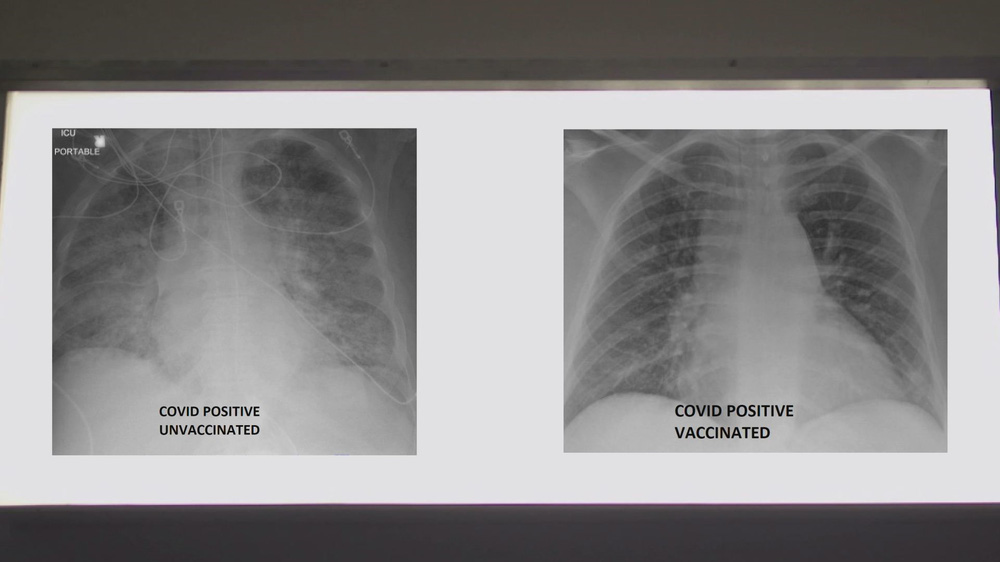

Một bác sĩ Mỹ vừa chia sẻ ảnh chụp phổi của 2 bệnh nhân COVID-19, nhấn mạnh về khả năng bảo vệ của vaccine COVID-19.

Để xem vaccine COVID-19 có thể giúp ích như thế nào, Bệnh viện SSM Health đã cung cấp hai bức ảnh chụp X-quang phổi của 2 bệnh nhân COVID-19 cho đài KSDK. Trong hai người này, một người đã được tiêm vaccine COVID-19, một chưa chưa tiêm.

Tiến sĩ Kamel đã xem phim chụp X-quang và giải thích chất màu trắng trong phổi mà bạn nhìn thấy chính là tác động của virus. Đó có thể là vi khuẩn, chất nhầy hoặc dịch tiết, tiến sĩ nói.

Tuy nhiên, tiến sĩ Kamel đã phân tích về sự khác biệt có thể thấy trên phim chụp X-quang.

Ông cho biết khi nhìn vào hình chụp X-quang của người chưa được tiêm vaccine COVID-19, ông đánh giá đây rất có thể một bệnh nhân cần được hỗ trợ.

"Họ chắc chắn ít nhất cũng cần oxy và đôi khi họ cần nhiều hơn thế. Họ có thể cần dùng máy thở hoặc được đặt nội khí quản, dùng thuốc an thần và về cơ bản là hỗ trợ sự sống", tiến sĩ Kamel nói.

Còn nếu bạn nhìn vào hình ảnh của người đã tiêm vaccine, bạn sẽ thấy nhiều màu đen hơn. Tiến sĩ Kamel giải thích: Khi phổi chứa đầy không khí, nó sẽ có màu đen trong phim X-quang. Như vậy, bức ảnh này có nhiều màu đen hơn ảnh trước.

Chủ nhân của phim X-quang này mắc COVID-19 dù đã được tiêm vaccine - một trường hợp hiếm khi xảy ra. Chỉ dưới 1% những người được tiêm vaccine bị nhiễm COVID-19.

So sánh ảnh chụp phổi của bệnh nhân COVID-19 không tiêm và có tiêm vaccine. Ảnh: KSDK